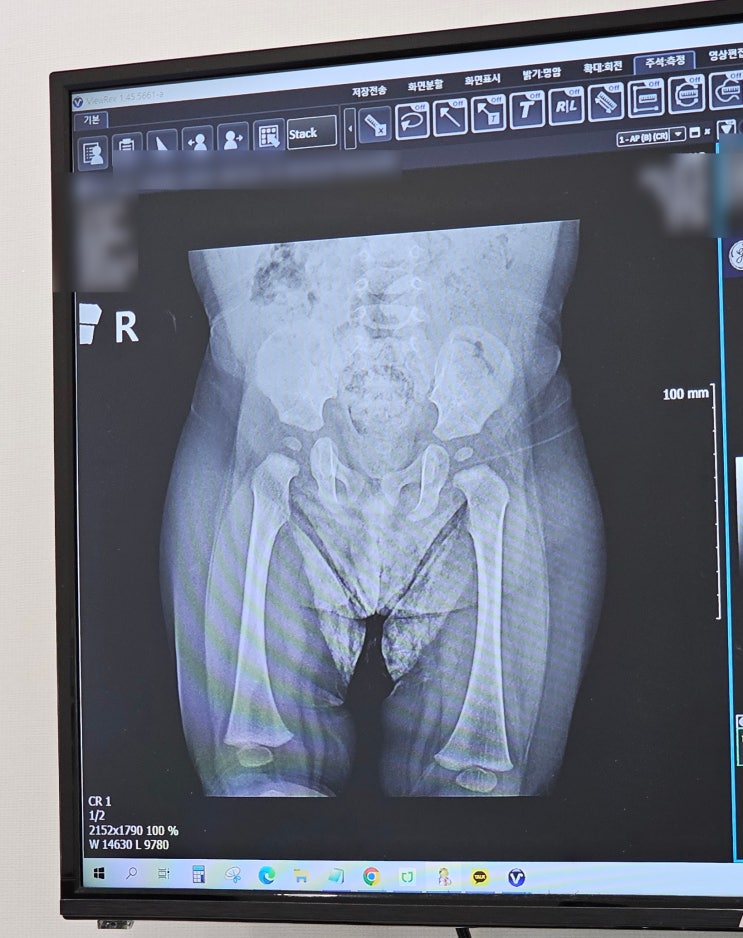

고관절 탈구, 고관절 이형성증 의심으로 인본병원 방문 (실비청구)

고관절 탈구, 고관절 이형성증 의심으로 인본병원 방문 (실비청구) 아기가 태어나면 국가에서 영유아 검진...